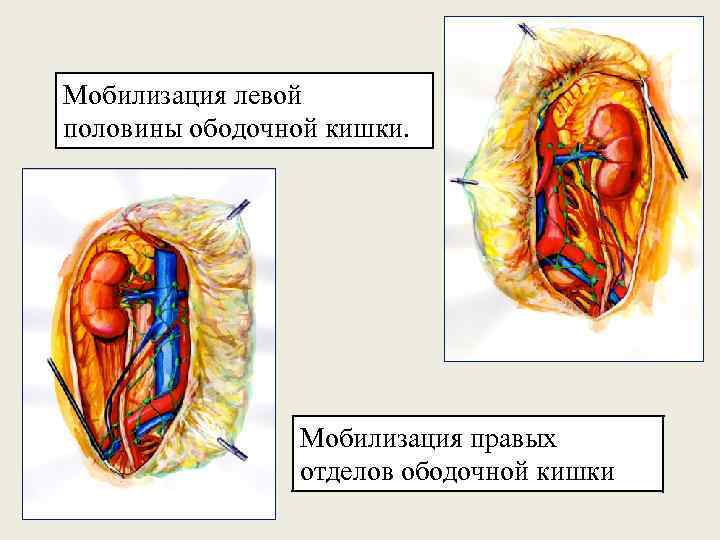

Мобилизация левой половины ободочной кишки. Мобилизация правых отделов ободочной кишки